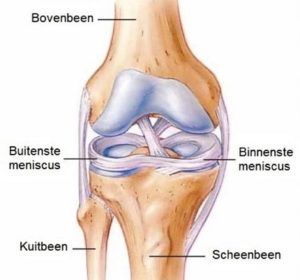

De meniscus is een halfcirkelvormige, rubberachtige schijf uit een speciaal soort kraakbeen, die zich bevindt tussen bovenbeen (femur) en onderbeen (tibia). Er is een binnenste C-vormige (mediale of interne) en een buitenste 0-vormige (laterale of externe) meniscus. Elke meniscus bestaat uit 3 delen: de achterhoorn, het corpus (body) en de voorhoorn. Tevens onderscheidt men in de meniscus drie zones: een buitenste 1/3 zone (de rode zone) met een goede doorbloeding, een middenste 1/3 zone (de rood-wit zone) met middelmatige bloedvoorziening en een binnenste 1/3 zone (de witte zone) zonder bloedvoorziening.

De binnenste meniscus is stevig verbonden met het kapsel van de knie, de buitenste meniscus daarentegen is niet strak verbonden met het kapsel en dus veel meer beweeglijk.

Anatomie van de meniscus in het kniegewricht Voorhoorn en achterhoorn van de meniscus Rode en witte zone van de meniscus - vaatvoorziening